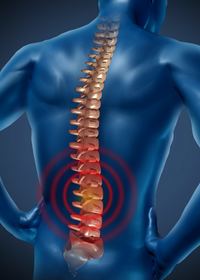

Wirbelblockaden Erkrankungen

Schmerzhafte Verspannungen und Wirbelblockierungen

schmerhafter eingeklemmter Nerv

schmerzhafte Gelenkwirbel durch Entzündungen und Bandscheibenvorwölbung

Was ist überhaupt eine Wirbelblockade?

Der normale Bewegungsspielraum des Wirbels ist eingeschränkt. Eine Blockade ist eine funktionelle Fehlstellung eines Wirbels bzw. die Blockade seiner Gelenke.

Treten Blockaden auf, verliert das Tier oder der Mensch, die Flexibilität der Wirbelsäule. Die Folge daraus sind Steifheit, Muskelverspannungen und eine enorme Beeinträchtigung der Leistungsfähigkeit. Blockaden führen häufig zur Unrittigkeit und Unbrauchbarkeit eines Pferdes und kann die Meridiane und somit die Funktion der dazugehöriger Organe einschränken. Das Gleiche im Sinne geschieht auch mit unseren Tieren.

Der Patient verspürt starke Schmerzen, die nach überall hin ausstrahlen können.

Was passiert bei aufkommenden Wirbelblockaden?

Die austretenden Nervenstränge sind bei Blockaden empfindlich gestört, lassen Schmerzen ausstrahlen, die bis zu den inneren Organen, Knochen und Muskeln fließen. Mangelnde Koordination können auch dazu führen, dass weitere Sehnen, Bänder und Gelenke verletzt werden.